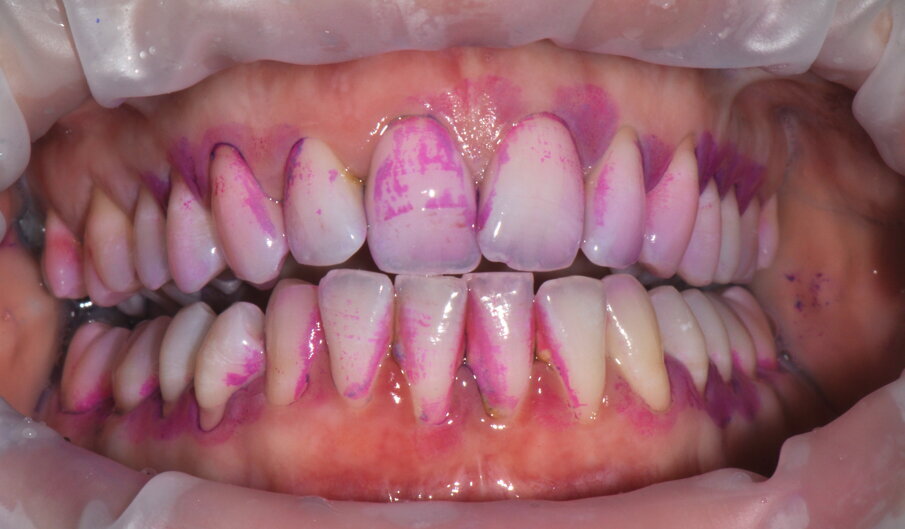

- Applicazione del rilevatore di placca bifasico: permette la distinzione fra i depositi di placca recenti da quelli meno recenti ( 1a-1c);

- Istruzione e motivazione all’igiene orale domiciliare guidati dal rilevatore di placca, mostrando visivamente al paziente l’attuale stato del suo mantenimento;

Figg. 1a-1c - Applicazione del rilevatore di placca che verrà usato come guida durante la terapia, nel versante vestibolare (1a), palatale (1b) e linguale (1c). Si noti lo scarso livello di igiene orale domiciliare e l’assenza di utilizzo dei presidi interdentali.